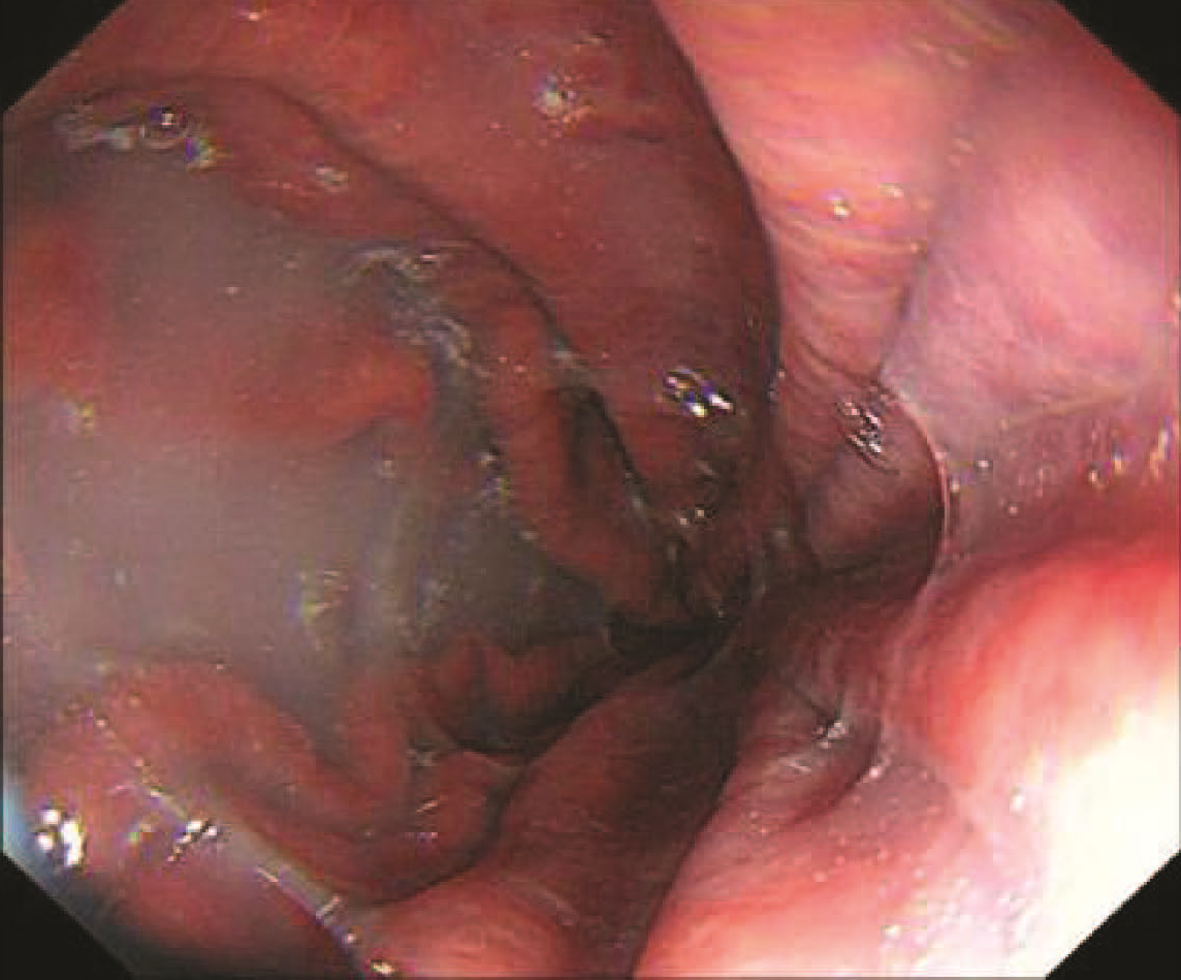

Endoscopic sequential ligation for treatment of esophageal and gastric varices with duodenal varices: A case report

Hao WEN, Zhaohui HE, Tong JIANG, Guoqing SHI

2023, 39(3): 637-639. DOI: 10.3969/j.issn.1001-5256.2023.03.024

Abstract(880) HTML (273) PDF (2676KB)(104)

Abstract: